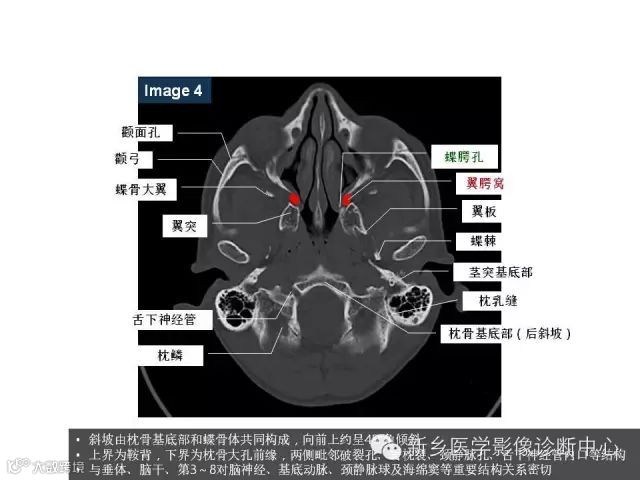

颅底孔道解剖详解

值得收藏!